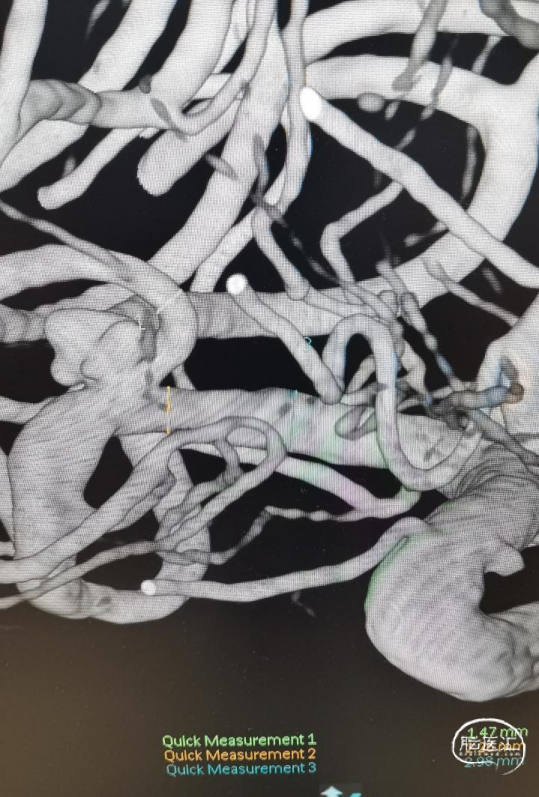

术前影像

CT显示广泛蛛网膜下腔出血,右侧侧裂池为著。

DSA示:右侧大脑中动脉分叉上干起始部宽颈动脉瘤,呈不规则分叶状,载瘤动脉管径纤细,角度锐利,载瘤动脉直径1.45mm,大脑中动脉直径2.26mm,动脉瘤大小约5.35mm×3.98mm×4.14mm。